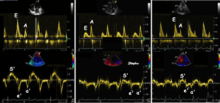

Systolic function

Peak systolic annular velocity (S') of the left ventricle is as close to a contractility measure as you can get by imaging [4](bearing in mind that any imaging method only measures the result of fibre shortening, without measuring myocyte tension). S' has become a reliable measure of global function[5][6][7][8] It shares the advantage of annular displacement, that it is reduced also in hypertrophic hearts with small ventricles and normal ejection fraction (HFNEF), which is often seen in Hypertensive heart disease, Hypertrophic cardiomyopathy and Aortic stenosis.[9]

Diastolic function

As the ventricle relaxes, the annulus moves towards the base of the heart, signifying the volume expansion of the ventricle. The peak mitral annular velocity during early filling, e' is a measure of left ventricular diastolic function, and has been shown to be relatively independent of left ventricular filling pressure.[12][13][14][15] If there is impaired relaxation (Diastolic dysfunction), the e' velocity decreases. After the early relaxation, the ventricular myocardium is passive, the late velocity peak a' is a function of atrial contraction. The ratio between e' and a' is also a measure of diastolic function, in addition to the absolute values.

During the two filling phases, there is early (E) and late (A) Blood flow from the atrium to the ventricle, corresponding to the annular velocity phases. The flow, is driven by the pressure difference between atrium and ventricle, this pressure difference is both a function of the pressure drop during early relaxation and the initial atrial pressure. In light diastolic dysfunction, the peak early mitral flow velocity E is reduced in proportion to the e', but if relaxation is so reduced that it causes increase in atrial pressure, E will increase again, while e', being less load dependent, remains low. Thus, the ratio E/e' is related to the atrial pressure, and can show increased filling pressure,[16][17][18] although with several reservations.[19][20] In the right ventricle this is not an important principle, as the right atrial pressure is the same as central venous pressure which can easily be assessed from venous congestion.[21][22]